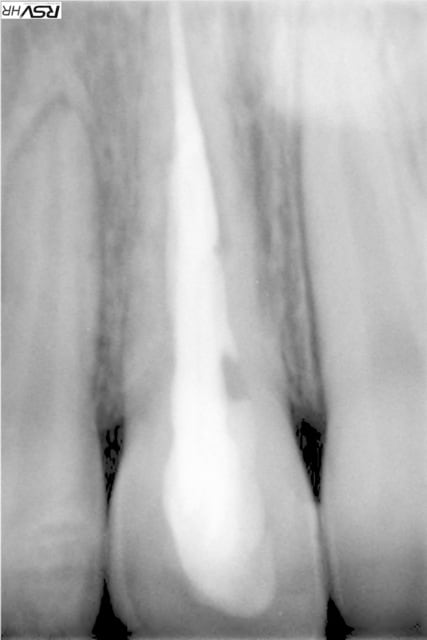

isabelleni

25/10/2013 à 00h33

voici la radio de la 21:

1° CAS une belle perf traitée avec du Biodentine. Résultat à 2 ans.

2°CAS expulsion - réimplantation immédiate - à 3 ans résorption interne - biodentine . le résultat est sans commentaire.

aîe,alors là tu me démoralises complètement...en fait j'essaie de sauver la dent de mon fils qui a été victime d'un accident il y a 12 ans.La dent est restée vivante une dizaine d'années,puis début de nécrose,dévitalisation et maintenant début de résorption...ta dernière radio était combien de temps après ta tentative de biodentine?